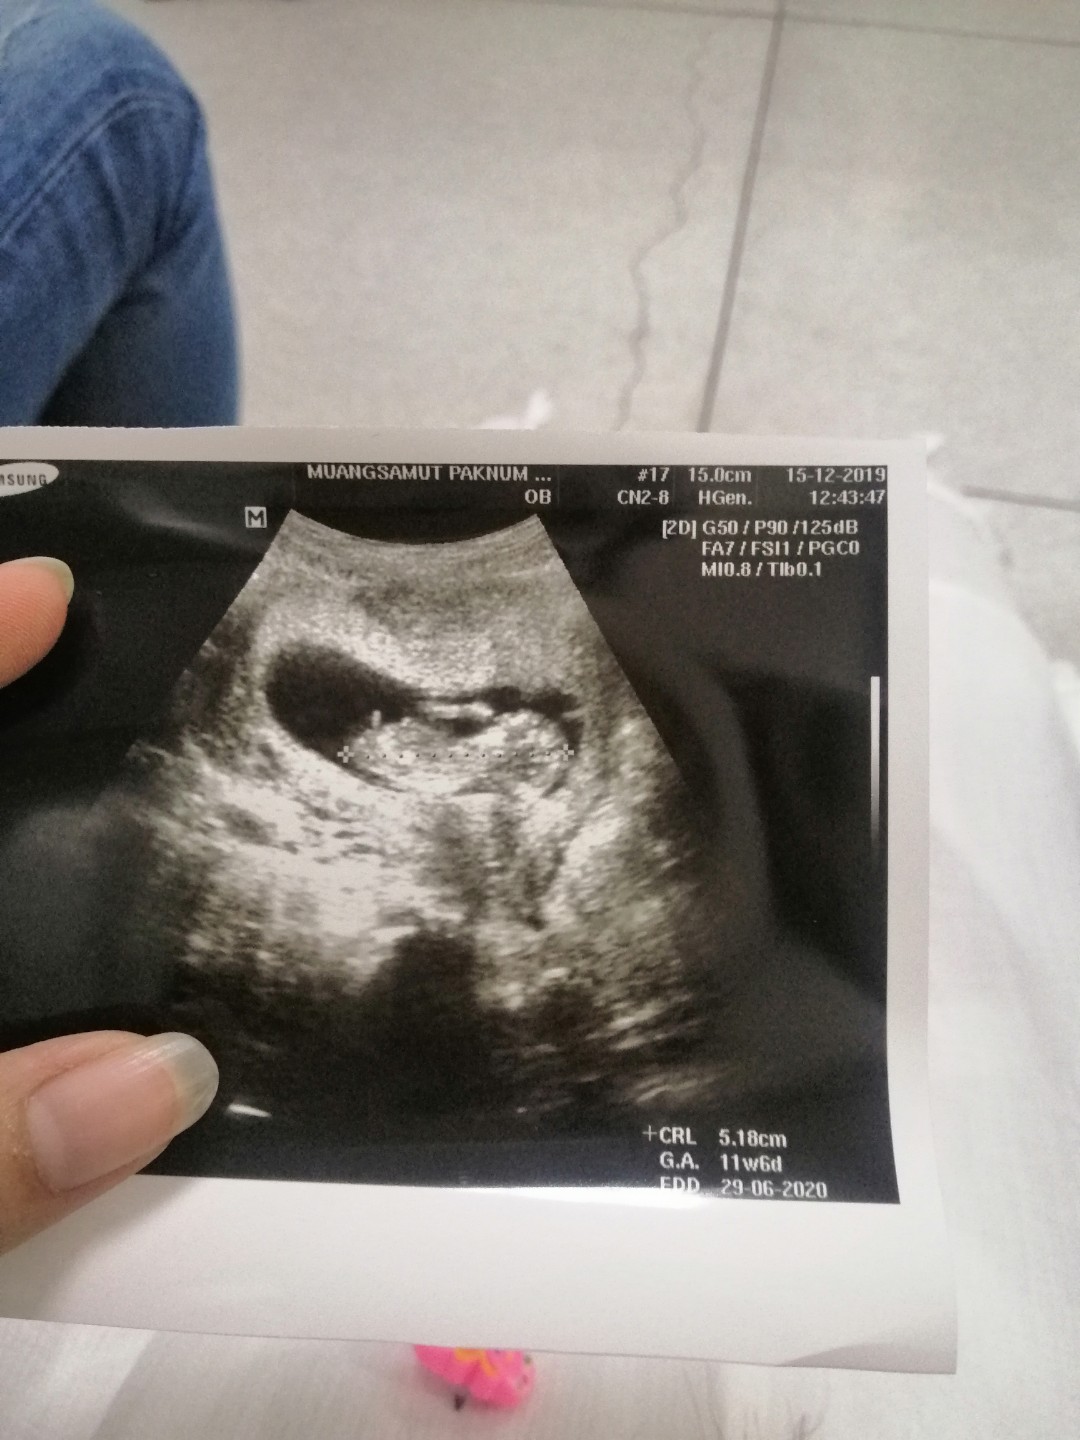

11w3d

Post reply image